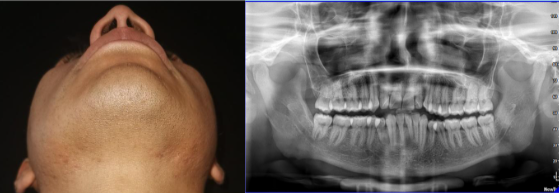

Se realizaron controles postquirúrgicos, tanto clínicos e imagenológicos, en la clínica de cirugía oral y maxilofacial de la UNAM al primer mes y, finalmente, al año de este proceso, podemos constatar una adecuada evolución con una correcta cicatrización y regeneración ósea en el lecho quirúrgico (Ver Figura 4).

Fotografía caudo-cefálica. Ortopantomografía.

A. Fotografía caudo-cefálica.

B. Ortopantomografía.